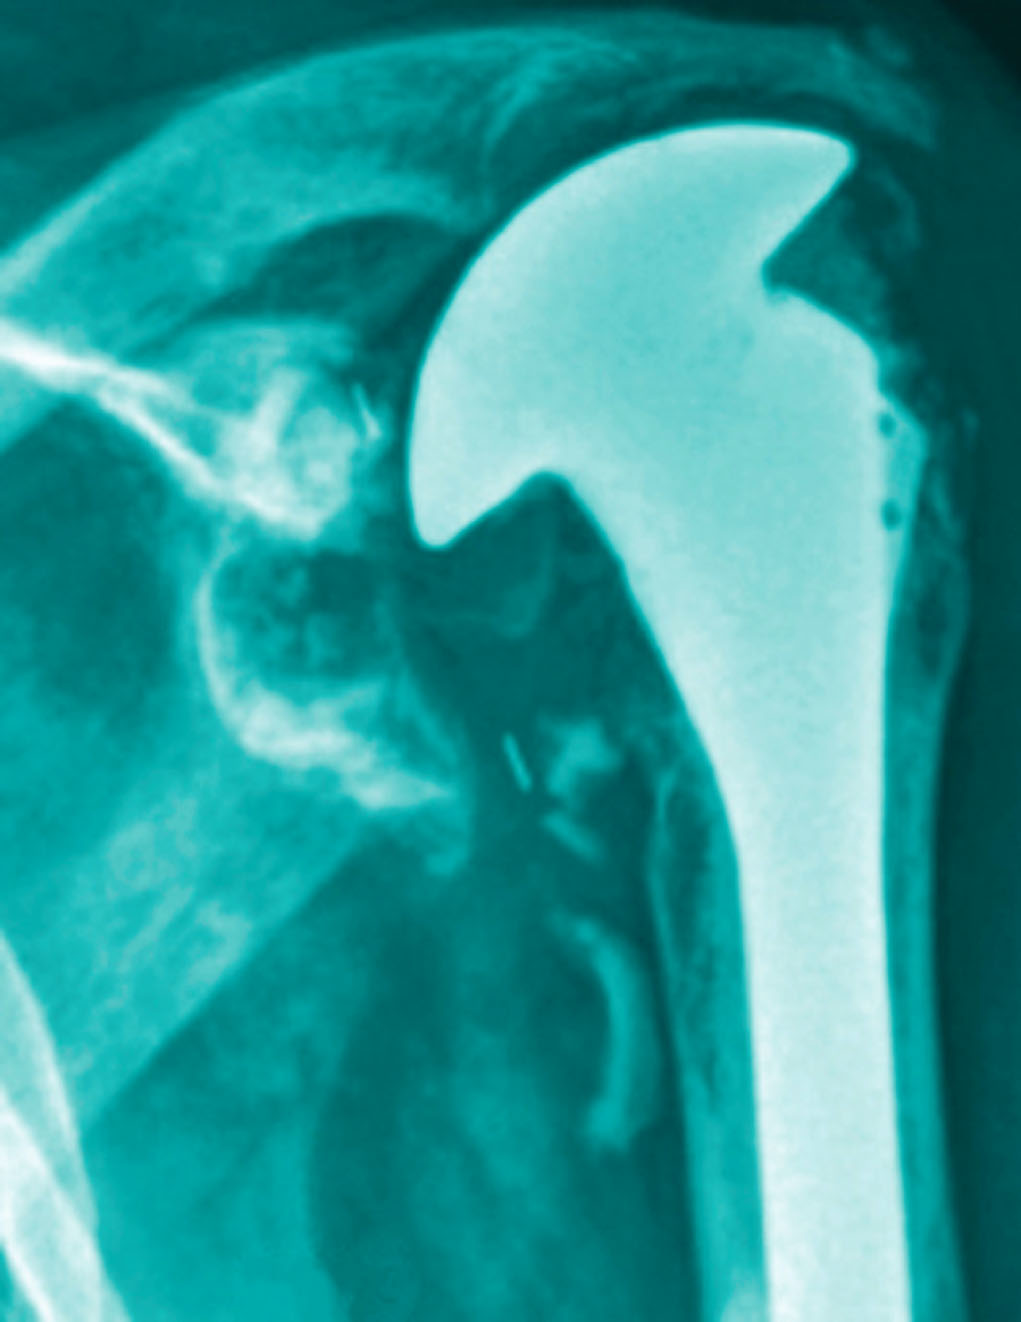

Is Shoulder Replacement More Painful Than Rotator Cuff Surgery . Shoulder replacement removes part or all. Both rotator cuff repair and shoulder replacement surgery are excellent operations for patients with shoulder pain. Which operation you need is dependent on what the cause of your. Pain is a likely side effect of both surgeries. Is shoulder replacement more painful than rotator cuff surgery? Total shoulder replacement, also known as total shoulder arthroplasty, is a procedure where portions of the bones in the shoulder joint are removed and replaced with. Studies have shown that both shoulder replacement and rotator cuff surgery provide lasting pain relief and. Rotator cuff surgery and shoulder replacement surgery are viable options for shoulder injuries and pain.

Total shoulder replacement, also known as total shoulder arthroplasty, is a procedure where portions of the bones in the shoulder joint are removed and replaced with. Is shoulder replacement more painful than rotator cuff surgery? Both rotator cuff repair and shoulder replacement surgery are excellent operations for patients with shoulder pain. Shoulder replacement removes part or all. Pain is a likely side effect of both surgeries. Rotator cuff surgery and shoulder replacement surgery are viable options for shoulder injuries and pain. Which operation you need is dependent on what the cause of your. Studies have shown that both shoulder replacement and rotator cuff surgery provide lasting pain relief and.